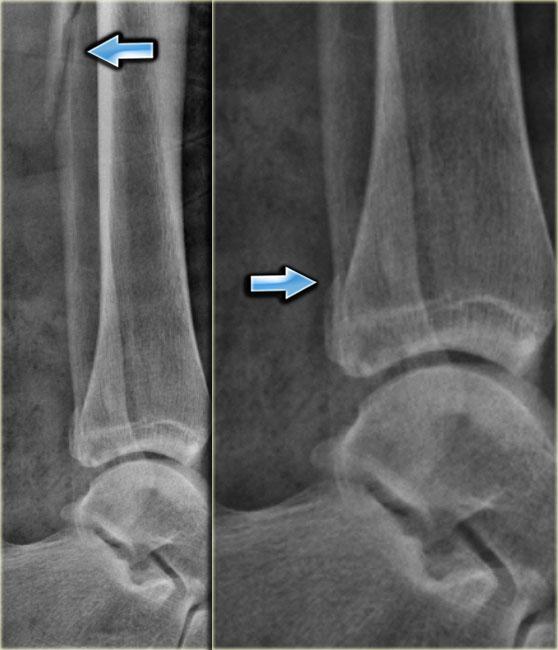

Đây là một ví dụ về gãy xương Weber C kèm theo gãy xương mác đoạn gần.

Lưu ý rằng trên phim X-quang cổ chân không thấy đường gãy xương.

Bạn có thể chẩn đoán nhầm đây chỉ là sưng nề phần mềm đơn thuần.

Thực tế đây là gãy xương cổ chân không vững, vì chắc chắn phải có kèm theo đứt dây chằng bên trong (giai đoạn 1), do đó vòng xương bị phá vỡ ở hai vị trí dẫn đến mất vững.

According to Lauge Hansen we are probably dealing with:

- Medial collateral band rupture

- Rupture of the anterior syndesmosis

- High fibula fracture

- and possibly a rupture of the posterior syndesmosis

Cuối cùng dây chằng chày mác sau bị đứt, hoặc có sự bong gân của mắt cá sau, còn được gọi là gãy mắt cá sau (mũi tên đỏ).

Khoang sáng phía trong chỉ giãn rộng nhẹ, nhưng dựa trên các giai đoạn của Lauge Hansen, chắc chắn phải có đứt dây chằng bên.